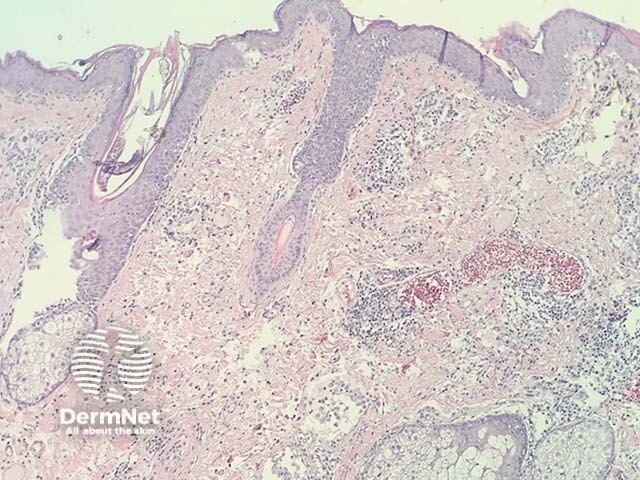

In intralymphatic histiocytosis, the histopathology shows dilated lymphatic spaces stuffed with histiocytes and associated lymphocytes (figures 1,2,3). There is often oedema of the surrounding dermis. The overlying epidermis is uninvolved. In cases occurring around the eyes, it is common to find Demodex species in follicular structures (figure 4).

Figure 1